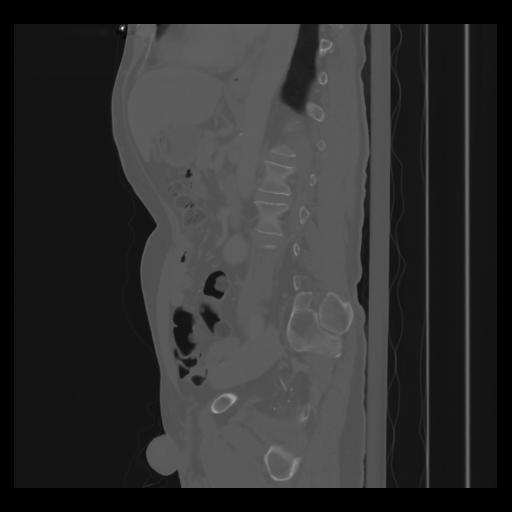

36 CUERPO,CE,Sagittal,3.000,CUERPO,Sagittal,